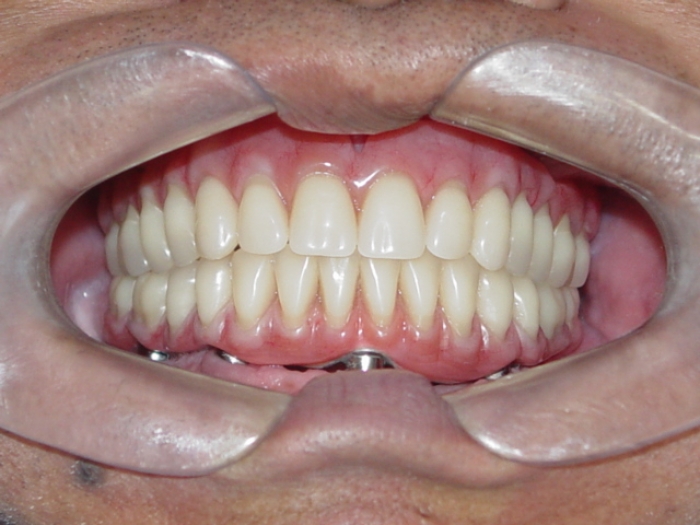

Prótese fixa inferior em resina

Sorriso final, do caso terminado em setembro de 2008